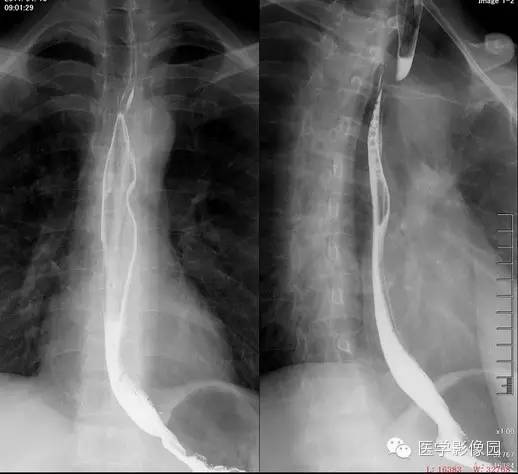

钡餐造影

道上段于主动脉弓上缘以上显示一条由左下向右上方斜行边缘光滑的螺旋形压迹,宽约1CM左右;局部可见血管搏动现象。食道粘膜皱襞规则完整,管壁柔韧度及管腔扩张正常,其以上的食管无明显扩张。